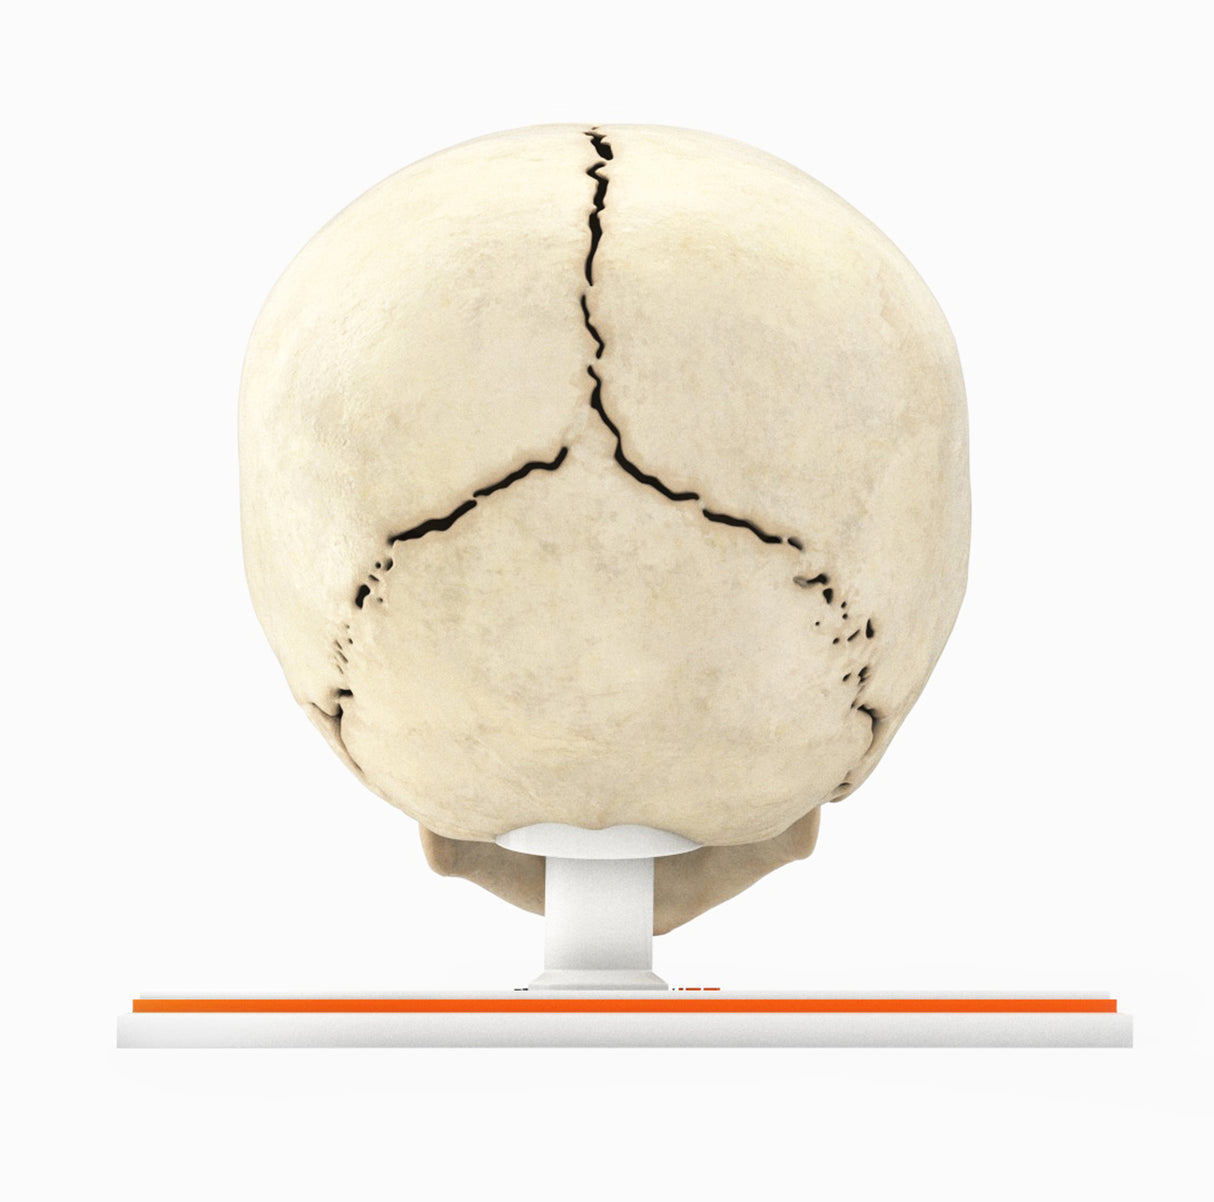

Infant Skull With Craniosynostosis of the Metopic Suture - Male, 8 Months

Infant Skull With Craniosynostosis of the Metopic Suture - Male, 8 Months

Craniosynostosis, a condition in which one or more cranial sutures in the infant skull prematurely mineralize and fuse before completion of brain development, with affected sutures:

Metopic synostosis (trigonocephaly) – The metopic suture separates two frontal bones in the cranial vault and runs from the nose to the sagittal suture at the top of the head. Premature fusion causes a triangular head shape, narrow in the front and broad in the back, with a metopic ridge at the midline of the forehead.

In most cases, the cause of craniosynostosis is unknown. Crouzon, Apert and Pfeiffer syndromes are the most common craniofacial syndromes, accounting for nearly two-thirds of syndromic cases. Most of these patients exhibit elevated intracranial pressure (ICP), hydrocephalus, optic atrophy, and respiratory, speech and hearing problems. Surgical management is common for primary craniosynostosis where there is restriction of brain growth and elevated ICP, typically within the first year of life.

Designed using MRI and CT imaging scans and the latest 3D printing technologies, in collaboration with Mayo Clinic.